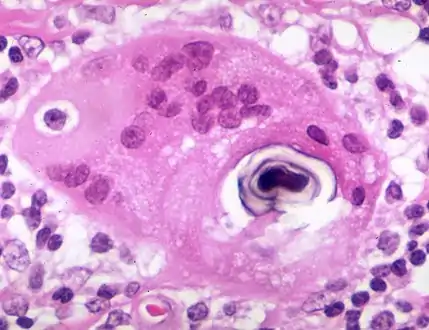

Histopathology

Sarcoidosis is characterized by the formation of non-necrotizing ("non-caseating") granulomas in various organs and tissues.[96] Giant cells, specifically Langhans giant cells, are often seen in sarcoidosis.[97] Schaumann bodies seen in sarcoidosis are calcium and protein inclusions inside of giant cells as part of a granuloma.[98] Asteroid bodies can be seen in sarcoidosis.[98] Hamazaki–Wesenberg bodies can be seen in lymph nodes and more rarely in lung biopsies with sarcoidosis and are inclusion bodies of lysosomes with protein, glycoprotein and iron.[99]

Schaumann body in sarcoidosis

Schaumann body in sarcoidosis.jpg.webp) Asteroid body in sarcoidosis